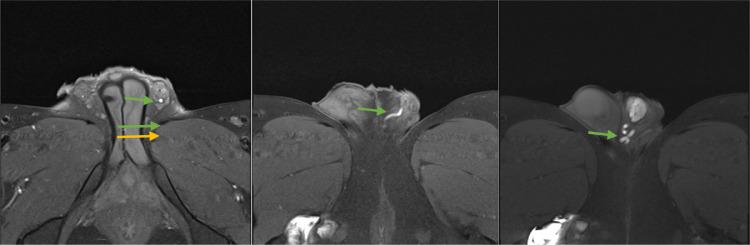

Zinner syndrome comprises a triad of unilateral renal agenesis, ipsilateral seminal vesicle cyst, and ejaculatory duct obstruction, which can be accompanied by additional abnormalities of the genitourinary tract in some cases. Patients may be asymptomatic or present with urinary, reproductive, and/or local pain symptoms. Diagnosis is most commonly achieved via MRI. Here, we present the case of an 18-year-old male previously diagnosed with unilateral renal agenesis, who presented with testicular and penile pain, along with urinary urgency and frequency. MRI of the abdomen and pelvis revealed all three components of Zinner syndrome as well as an ectopic ureter emptying into the seminal vesicle. Our case adds to the existing limited literature on this rare syndrome and broadens the understanding of how this syndrome can present both clinically and radiologically.

齐纳综合征包括单侧肾缺如、同侧精囊囊肿和射精管梗阻三联征,某些情况下可伴有泌尿生殖道的其他异常。患者可能无症状,或出现泌尿系统、生殖系统和/或局部疼痛症状。诊断最常用的方法是磁共振成像(MRI)。在此,我们报告一例18岁男性病例,该患者此前被诊断为单侧肾缺如,现出现睾丸和阴茎疼痛,伴有尿急和尿频。腹部和盆腔的MRI显示了齐纳综合征的所有三个组成部分,以及一条异位输尿管排入精囊。我们的病例补充了关于这种罕见综合征的现有有限文献,并拓宽了对该综合征在临床和影像学上表现的认识。